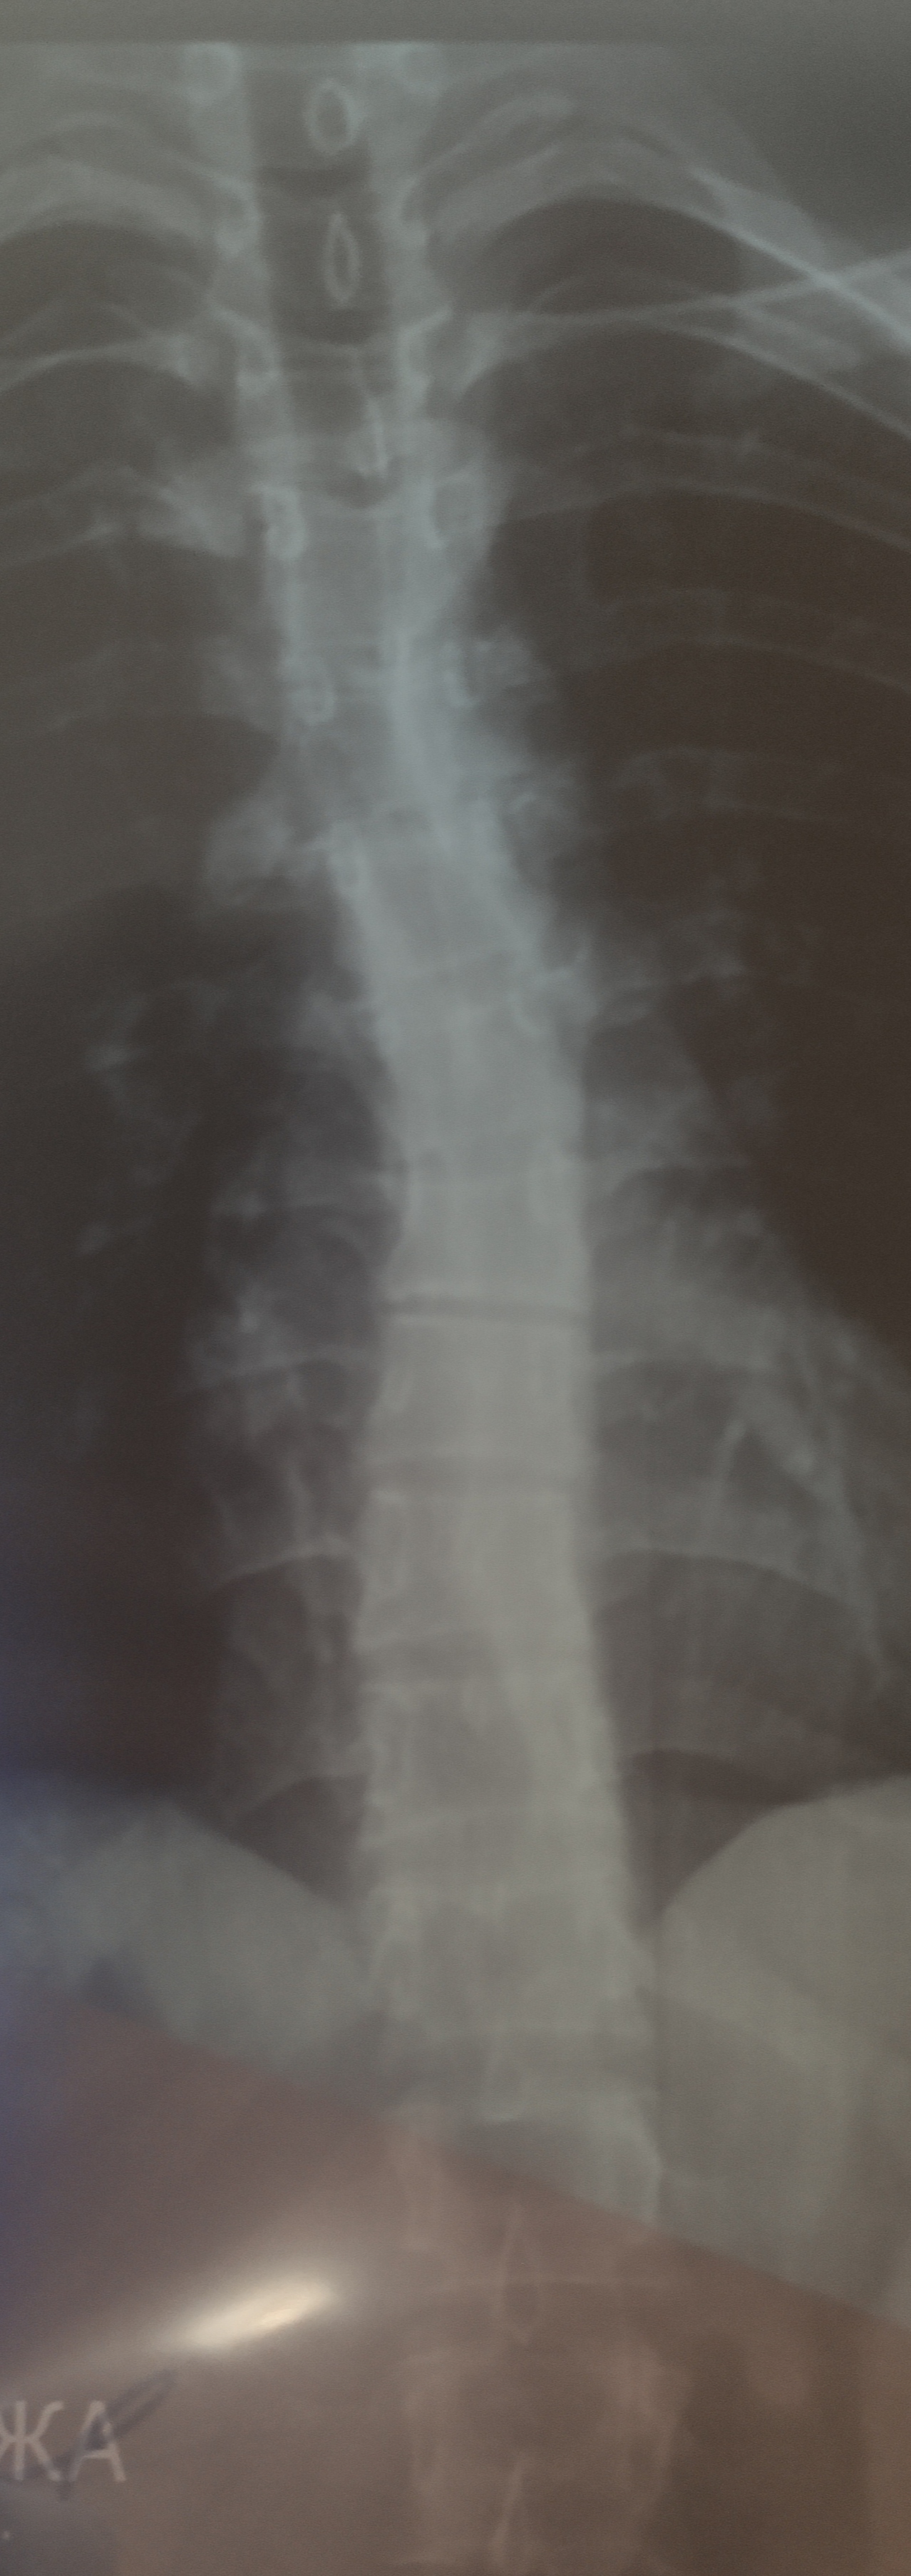

Здравствуйте, спасибо за быстрый ответ, к сожалению не могу сказать точно про метод измерения угла, но у меня имеются снимки ГОП лёжа, могли бы Вы на глаз определить сходится ли данные с углом искривление, либо все же меньше нужного

Вложения

Mischa писал(а):Здравствуйте, спасибо за быстрый ответ, к сожалению не могу сказать точно про метод измерения угла, но у меня имеются снимки ГОП лёжа, могли бы Вы на глаз определить сходится ли данные с углом искривление, либо все же меньше нужного

К сожалению, я не врач-рентгенолог и не разбираюсь в чтении рентгенографий, а осуществляю базовую консультацию по уже готовым медицинским документам.